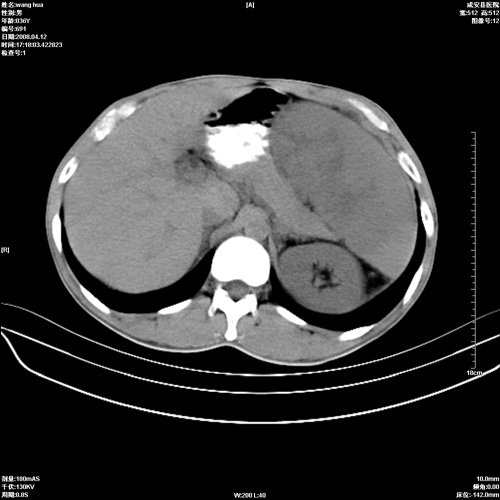

标题: CT12809:男36岁,自感上腹胀5天,B超诊断为脾肾之间占位,血 [打印本页]

标题: CT12809:男36岁,自感上腹胀5天,B超诊断为脾肾之间占位,血

请各位老师先分析一下定位 明天做增强

脾脏明显增大,其内见巨大低密度灶,境界不清,病史较短,考虑恶性病变脾血管内皮细胞肉瘤可能。建议增强扫描与脾脏淋巴瘤及血管瘤鉴别。